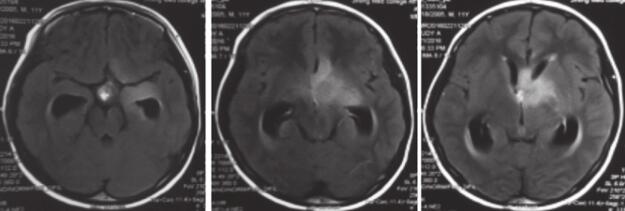

患者入院后完善术前检查,于2016年3月23日全麻下行鞍上病灶活检术。患者术后病理提示细胞密度高(图2),核异性大,核分裂随处可见,多核聚。ATRX(+),有内皮增生,无坏死,GFAP阳性,MIB-1阳性10%左右,NeuN弥漫强阳性,Olig2阳性,提示胶质来源,Sustan阳性,但是始终未找到坏死,核异型明显,最终诊断为(鞍区)胶质母细胞瘤(WHOⅣ级)。

图2 患者术后病理:HE提示患者细胞密度大,核异型大,核分裂处随处可见;ATRX阳性;GFAP阳性;MIB-1 10%左右